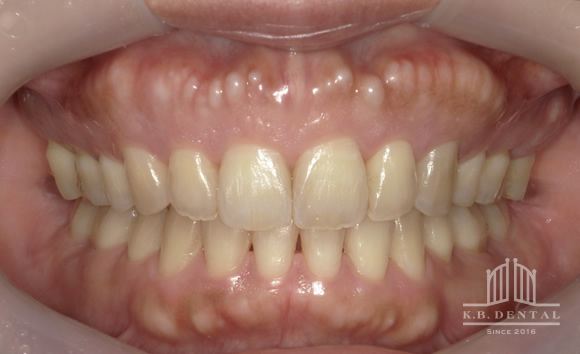

口蓋隆起 症例4(正中口蓋隆起)

口蓋の正中に発生した骨隆起です。静脈麻酔で約1時間半程度要します。

料金

静脈内鎮静法による麻酔代込み:約20万円(保険適用外)